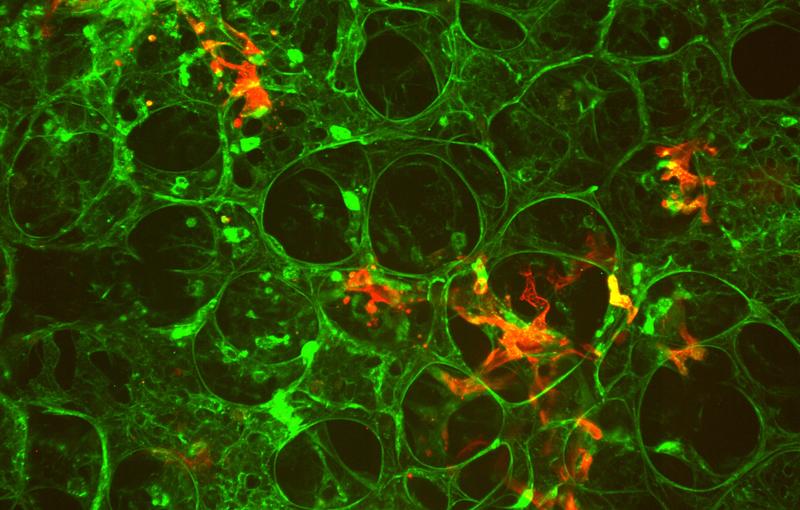

The combination of these systems with in vivo imaging in two animal models (zebrafish and mouse) enables the team to track their behaviour in the circulatory system. The researchers demonstrate that viscosity, rather than elasticity, determines whether circulating objects enter small vessels, where they come to a standstill, and how they extravasate, invading the surrounding tissues.

Furthermore, they show that viscosity is required for efficient extravasation through endothelial remodeling. At the same time, they find that mechanical properties which support extravasation do not necessarily support later metastatic growth.